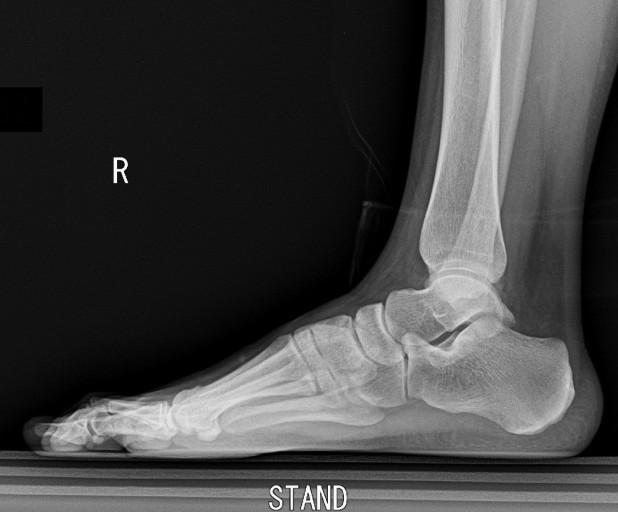

8. 발바닥에 딱딱한 결절

일부 환자들은 발꿈치에 결절이 생길 수 있습니다. 결절은 발꿈치 뼈에 작은 돌출부위로, 족저 근막염이 장기화되면 나타날 수 있습니다. 이 결절은 발꿈치를 눌렀을 때 통증을 유발합니다.